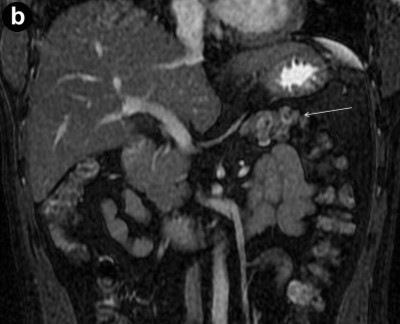

A 35-year-old lady investigated for recent onset of diabetes mellitus. She had no family history of diabetes mellitus. She had no history of pain abdomen, hepatobiliary disease or viral illness in childhood. She had ultrasound examination one month earlier at another institution which was interpreted as normal. Ultrasound examination at our institution revealed normal situs with visualization of pancreatic head. The body and tail were not visualized. She had polysplenia and bicornuate uterus. On non-contrast computed tomography examination the pancreatic head was enlarged in size with speckled calcification in the parenchyma (Figure 2a). The pancreatic body and tail were absent. The space anterior to splenic vein was occupied by stomach and small bowel loops (Figure 2bcd). On CECT examination there was homogeneous enhancement of the head with lobulated lateral contour (Figure 2e). The discrete lobule at head measuring 22 mm approximately was posteriorly oriented in relation to superior pancreaticoduodenal artery (type II). The liver, gallbladder and kidneys were normal. On MRCP examination two short pancreatic ducts, one ventral duct and other proximal part of dorsal duct were visualized (Figure 2f). None of these ducts were dilated. The duct at body and tail region was absent confirming the diagnosis of partial agenesis of dorsal pancreas. She was treated with insulin.

Figure 2. Case #2. a. Axial non-contrast computed tomography image depicts focal calcification (arrow) in the head of pancreas. b. Axial CECT scan image shows dependent stomach sign (thick arrow). c. Axial T1W fat saturated spoiled gradient MR image depicts bowel loops (thin arrow) in distal pancreatic bed having same signal intensity to pancreatic head (thick arrow). d. Axial T2W fast spin echo MR image depicts bowel loops (thin arrow) in distal pancreatic bed having different signal intensity from pancreatic head (thick arrow). e. Axial CECT image depicts type II contour bulging of pancreatic head (asterisk), anterior superior pancreaticoduodenal artery (thick arrow), focal calcification (thin arrow). f. Three dimensional volume rendered MRCP image demonstrates two pancreatic ducts, ventral duct (thick arrow) having shorter length compared to dorsal duct (thin arrow). |